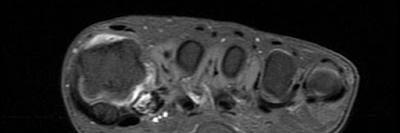

Observador de los pies, aprendiendo de pies y tratando de tratar pies. Sports podiatrist,Football and Running injury prevention. Lower limb Biomechanic.